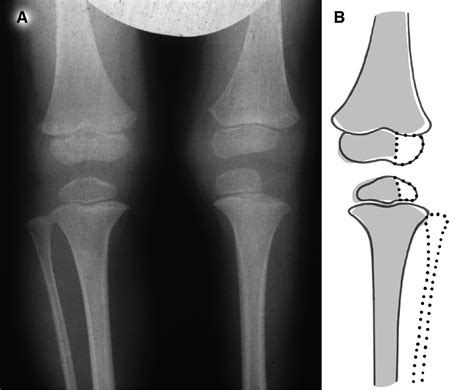

The epiphysis is the rounded end of a long bone, separated from the main shaft (diaphysis) by a layer of cartilage known as the epiphyseal plate or growth plate. This plate is responsible for the longitudinal growth of bones during childhood and adolescence. The epiphysis itself is composed of spongy bone and is covered by a thin layer of articular cartilage, which allows for smooth movement at the joints.

The epiphysis plays a pivotal role in the growth and development of children. The epiphyseal plate acts as a growth zone, where new bone tissue is formed through a process called endochondral ossification. This process involves the replacement of cartilage with bone tissue, leading to the elongation of the bone. The epiphysis continues to grow until the end of puberty, when the epiphyseal plate fuses with the diaphysis, marking the end of longitudinal bone growth.

• Growth Disturbances: Injuries to the epiphyseal plate can lead to growth disturbances, resulting in limb length discrepancies or angular deformities.